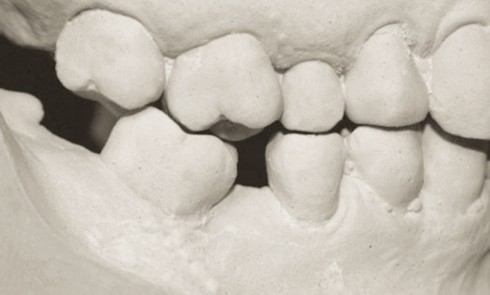

Article réservé à nos abonnés Les bridges collés cantilever en vitrocéramique renforcée au disilicate de lithium

L’édentement unitaire antérieur pose le difficile challenge de l’intégration esthétique au niveau prothétique. Les situations de trauma et celles d’agénésie...

Article réservé à nos abonnés Le cantilever : une nouvelle géométrie pour les bridges collés

Avec l’avènement de l’implantologie et son développement rapide, il peut sembler difficile de laisser une place aux bridges collés lorsqu’il...